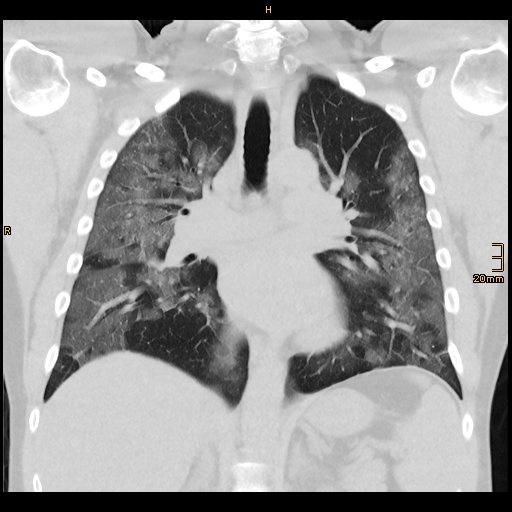

Sars Cov 2 Vernarbte Lunge Als Folge Zm Online

Sars Cov 2 Wie Das Virus Den Korper Verwustet Spektrum Der Wissenschaft

Obduktionen Deuten Auf Embolien Und Thrombosen Hin Gesundheit Sz De

Covid 19 Wie Die Viren Die Lunge Fruhzeitig Schadigen

Coronavirus So Schadigt Covid 19 Bei Schweren Verlaufen Die Lunge Welt